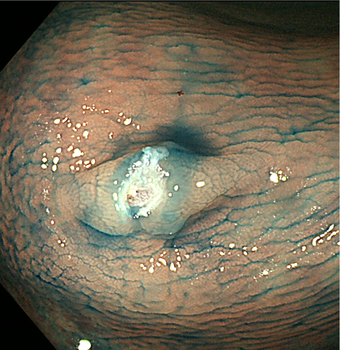

①大腸内視鏡検査

肛門から大腸に内視鏡を挿入して大腸内を直接調べる検査です。大腸内に便が残っていると十分な観察ができません。前日から食事制限が必要で、検査当日には腸管洗浄液を1〜2リットル飲み、腸管内をきれいにしてから検査を行います。通常検査は10-20分程ですが、検査には多少の苦痛を伴うため、当院では希望される方には鎮静剤を使用して検査を行っています。大腸内視鏡検査では、大腸がんや大腸ポリープを見つけることができます。

図 大腸がん